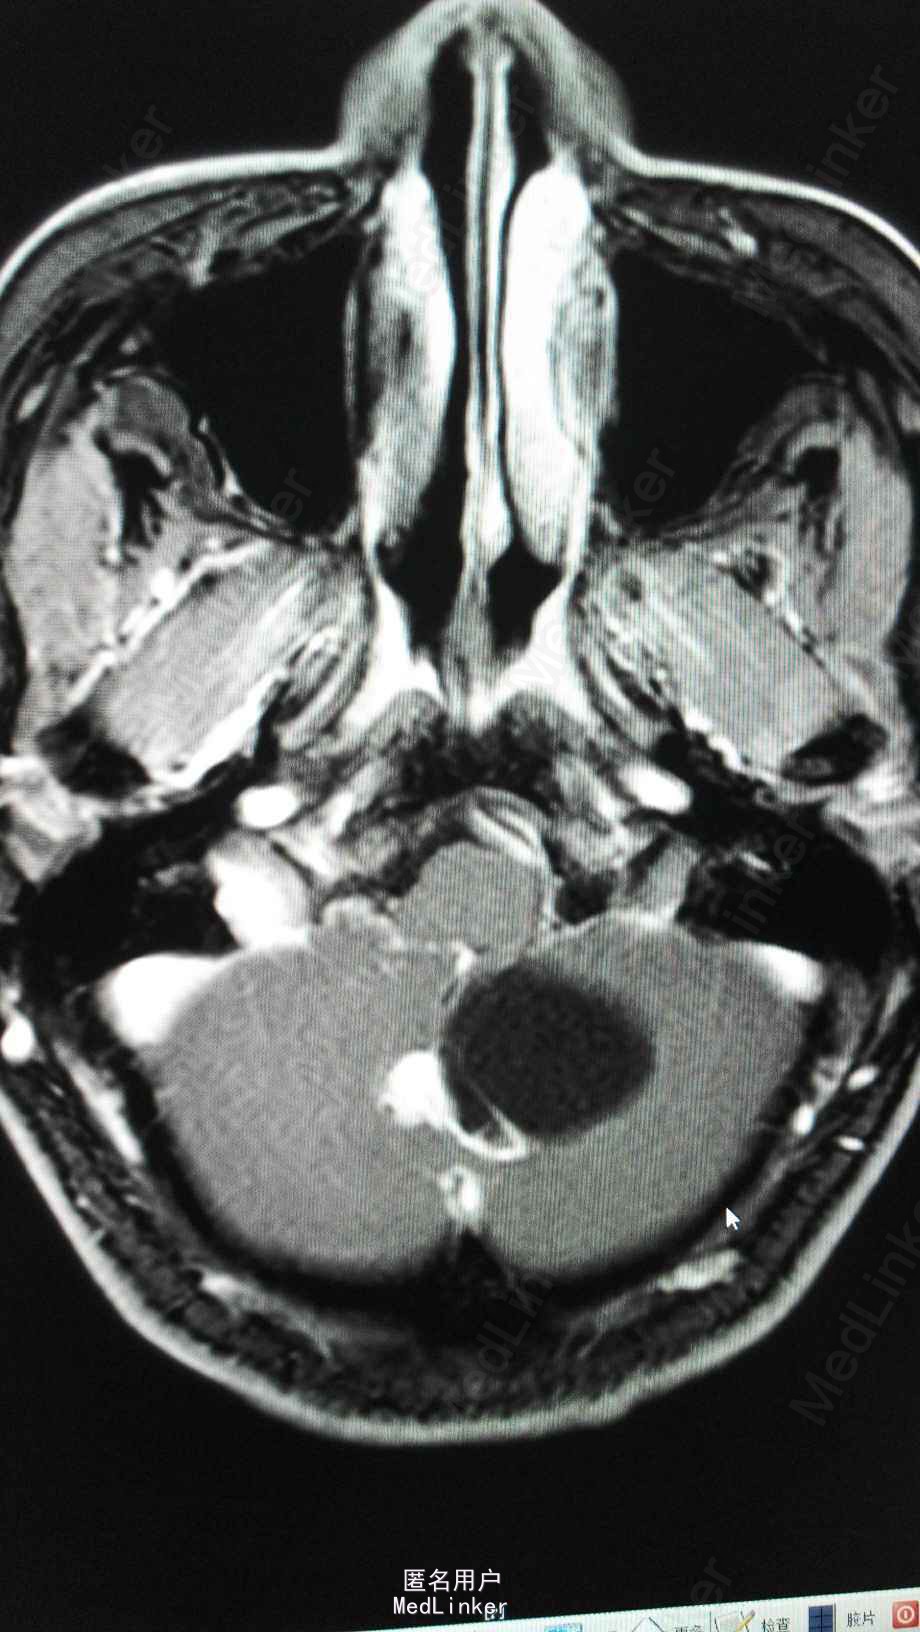

头颅MRA:小脑蚓部占位,血管母细胞溜可能性大;左椎动脉颅内段局部轻度狭窄;左侧大脑前动脉A1段稍细。